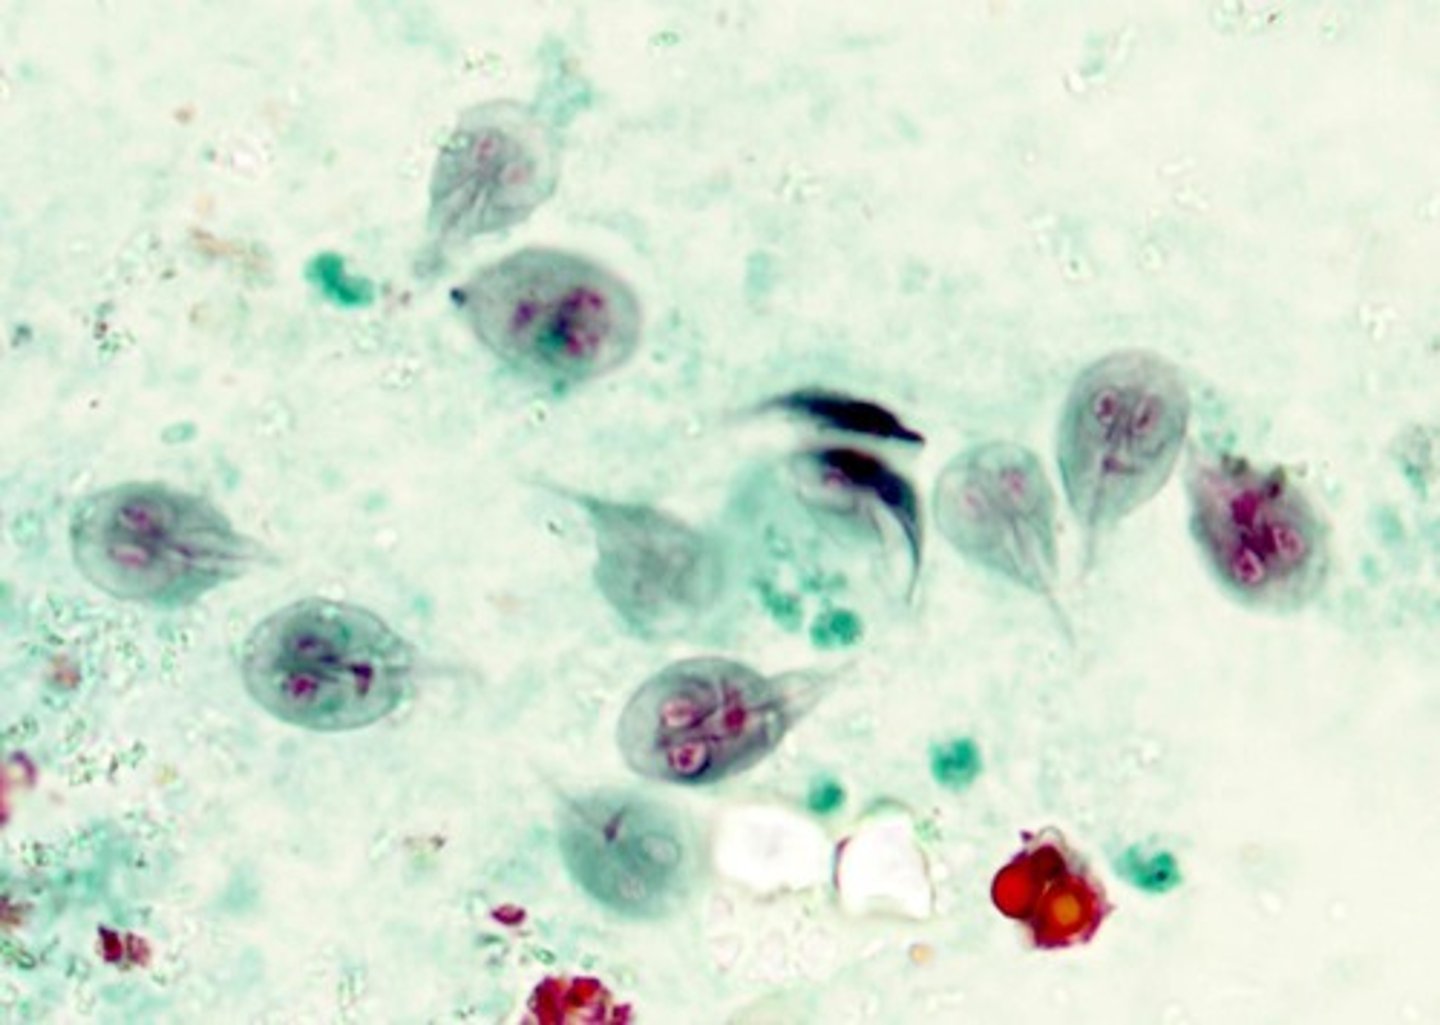

Trophozoites (Giardia duodenalis)

Kite shaped with central axoneme, 2 nuclei, flagella not always visible.

Cysts (Giardia duodenalis)

4 nuclei along central axoneme.